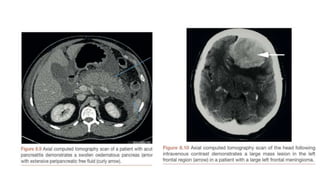

CT scan

- Method of cross sectional imaging

- CT uses a computer to create an image from an integration of multiple X-rays

exposures taken in a circle round the patient

- Heavy ionising radiation dose

- Parts : Gantry, X-ray source,detectors table

MRI

- Newest of the imaging techniques

- Does not use ionising radiation

- Parts : magnet , radio frequency coil , table

- Principle : Body tissues consist of protons and electrons. In a strong uniform

magnetic field such as a MRI scanner , these nuclei align themselves with the

main magnetic field.A brief radio frequency pulse is applied to alter the motion

of nuclei. When removed , the nuclei realign with the main magnetic

field,emitting energy.

CT scan - Methodof cross sectional imaging - CT uses a computer to create an image from an integration of multiple X-rays exposures taken in a circle round the patient - Heavy ionising radiation dose - Parts : Gantry, X-ray source,detectors table